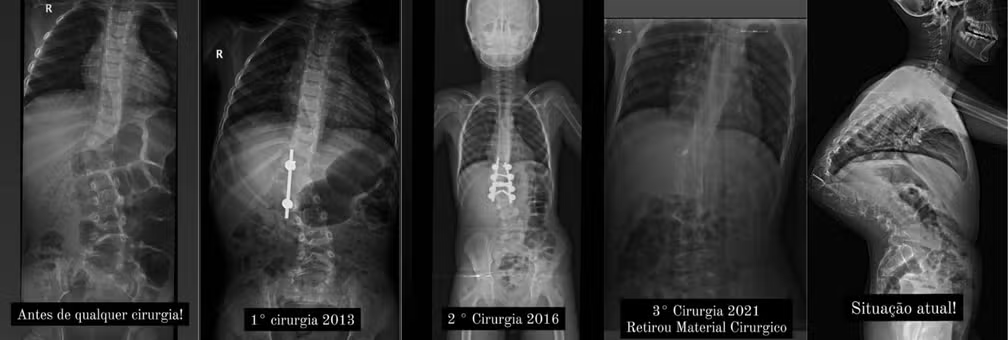

Murilo já passou por três cirurgias anteriores para tentar corrigir os problemas em sua coluna, mas uma delas resultou em complicações graves devido ao rompimento do material utilizado, causando uma infecção bacteriana.

Menino com curvatura de 127º na coluna já realizou três cirurgias — Foto: Arquivo Pessoal

Suélen Bernardo Arruda, moradora de Lupércio, cidade do interior de São Paulo com aproximadamente 3.981 habitantes, que fica a 71 quilômetros de Ourinhos (SP) está em uma corrida contra o tempo para arrecadar fundos e custear uma cirurgia vital para seu filho, Murilo, de 15 anos. Murilo sofre de cifoescoliose congênita, uma condição que resulta em uma curvatura de 127 graus na coluna vertebral, comprometendo sua saúde e qualidade de vida.

A cifoescoliose, uma associação de cifose e escoliose na coluna vertebral, é uma condição congênita que pode comprimir órgãos vitais como pulmão e coração, afetando a saúde do paciente desde o nascimento.